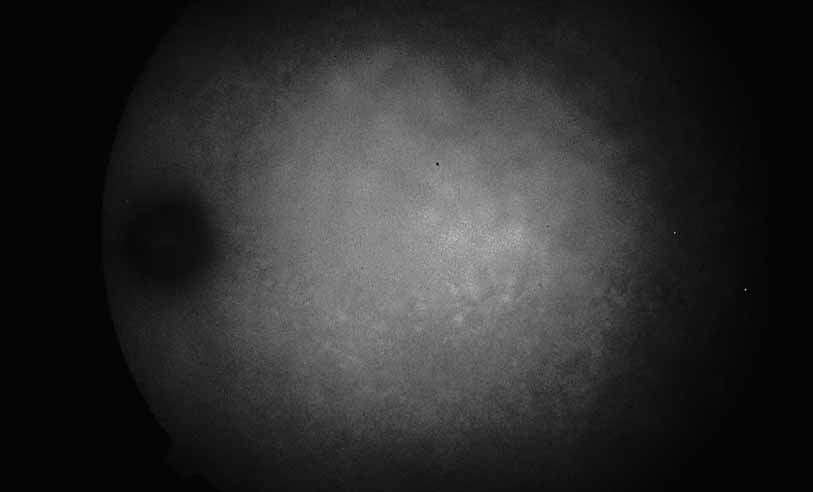

Fig. 1 Serpiginous choroiditis. Early frame of the fluorescein angiogram shows hypofluorescent and hyperflourescent patches extending outward from the optic nerve in a serpiginous pattern (Courtesy of Joseph Michaelson).

Fig. 2 Serpiginous choroiditis. Late frame of the fluorescein angiogram shows extensive staining of previously hypofluorescent zones, with continued hypofluorescence, characteristic of the acute phases of serpiginous choroiditis (Courtesy of Joseph Michaelson).